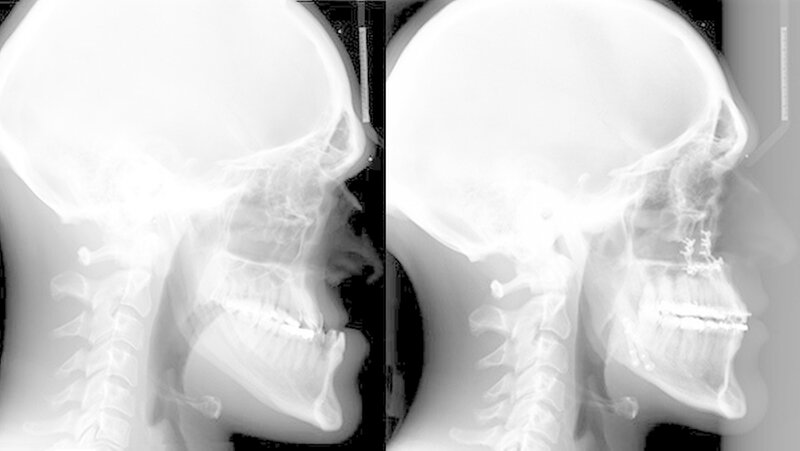

Das deutlich harmonischeres Profil drei Monate nach der Operation: Im Mai des nachfolgenden Jahres wurden die Metallplatten in einem ambulanten Eingriff wieder entfernt. Eine Multibandapparatur hält die Zähne noch "in der Reihe". Der Patient kann heute dank der individuellen innovativen Behandlung ein normales Leben führen, die Gesichtsästhetik und seine Kaufunktion sind vollständig wiederhergestellt.